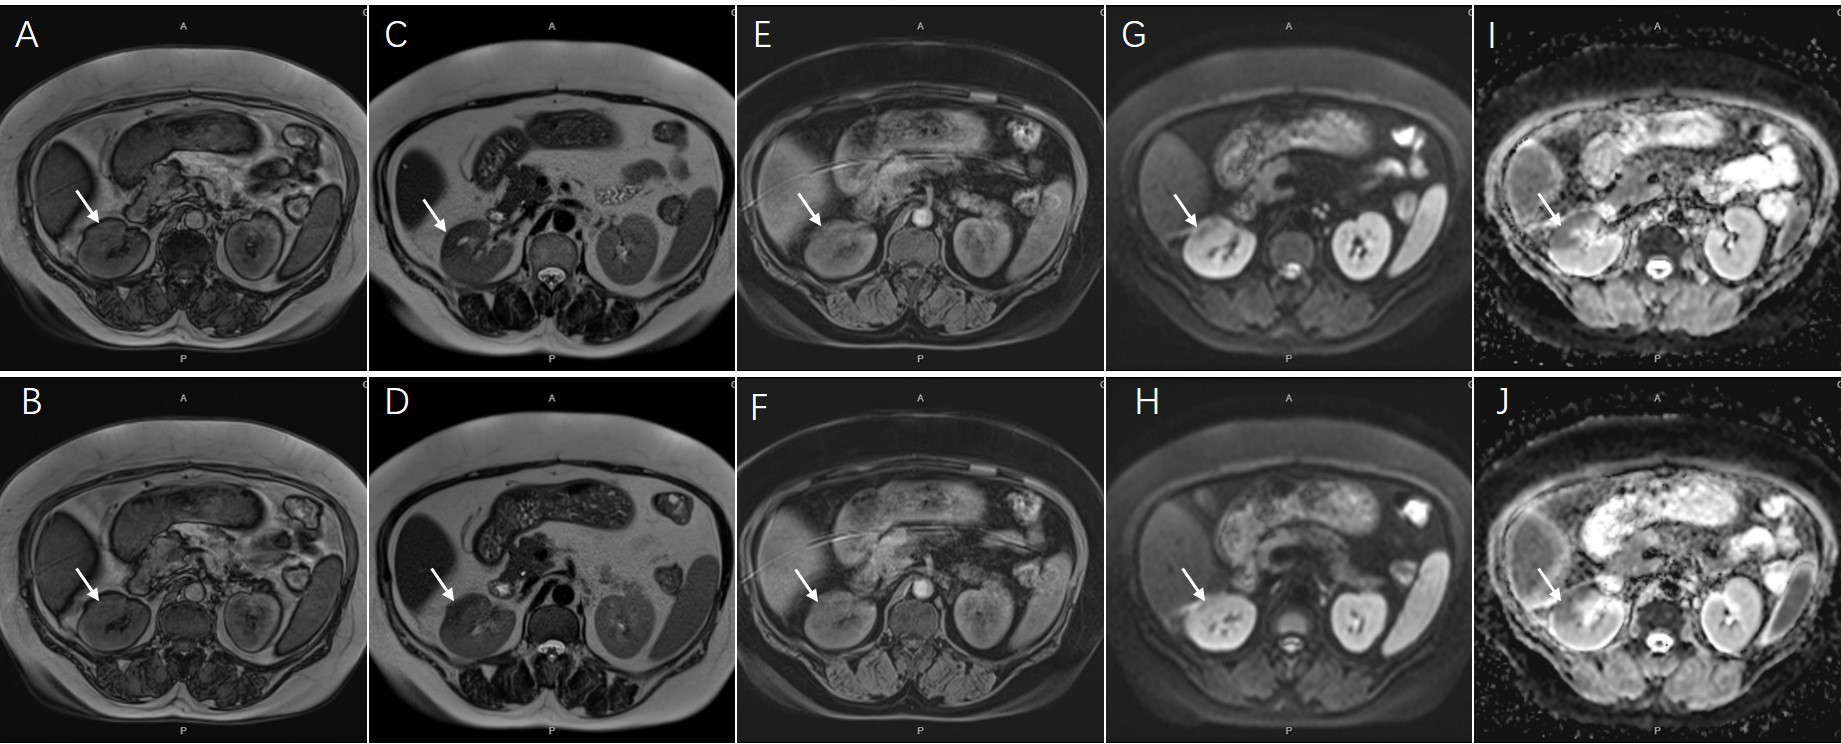

Contrast-enhanced CT revealed a multiple low-density lesion with marginal haziness in the right kidney (Figure 1). The enhancement degree was similar to that of the renal parenchyma in both the arterial (Figures 1A, B) and venous (Figures 1C, D) phases but was lower in the excretory phase (Figures 1E, F). CT primarily indicated an inflammatory lesion, but a tumor was also considered. On MRI (Figure 2), T2-weighted imaging revealed a mass with low signal intensity and unclear margins in the exterior of the middle pole of the right kidney (Figures 2C, D). In the cortical phase, the enhancement degree was comparable between the lesion and the surrounding kidney cortex, while an area with a slightly lower signal was located in the center of the lesion. The central area showed progressive enhancement in the delayed phase, and the retroperitoneal lymph nodes were homogeneously enhanced (Figures 2E, F). A diffusion-weighted imaging sequence revealed patchy enhancement of the lesion, with a lower signal in the center (Figures 2G, H). In summary, MRI indicated a diagnosis of a renal tumor (oncocytoma or chromophobe cell carcinoma), although inflammatory lesions could not be excluded.

Figure 2

Magnetic resonance imaging showed an inhomogeneous lesion approximately 44x23mm in diameter [(A, B), coronal T1-weighted image; (C, D), coronal T2-weighted image, arrows]. The central area presented progressive enhancement in delayed phase [(E, F), arrows]. The lesion also showed an opposite signal found in center on diffusion-weighted sequences [(G, H), arrows]. The ADC map on corresponding areas presented low signal appearance [(I, J), arrows].